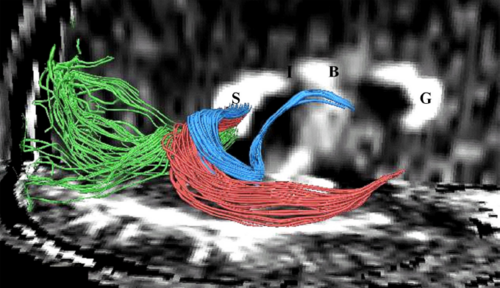

The Application of DTI to Investigate White Matter Abnormalities in Schizophrenia

Publication: Ann. N.Y. Acad. Sci. 2005; 1064:134–148. PDF

Authors: Marek Kubicki, Carl-Fredrik Westin, Robert W. McCarley, and Martha E. Shenton

Institution: Clinical Neuroscience Division, Laboratory of Neuroscience, Boston VA Healthcare System–Brockton Division, Department of Psychiatry, Harvard Medical School, Brockton, Massachusetts, USA

Background/Purpose: Schizophrenia is a serious and disabling mental disorder that affects approximately 1% of the general population, with often devastating effects on the psychological and financial resources of the patient, family, and larger community. The etiology of schizophrenia is not known, although it likely involves several interacting biological and environmental factors that predispose an individual to schizophrenia. However, although the underlying pathology remains unknown, it has been believed that brain abnormalities would ultimately be linked to the etiology of schizophrenia. This theory was rekindled in the 1970s, when the first computer-assisted tomography (CT) study showed enlarged lateral ventricles in schizophrenia. Since that time, there have been many improvements in MR acquisition and image processing, including the introduction of positron emission tomography (PET), followed by functional MR (fMRI), and diffusion tensor imaging (DTI). These advances have led to an appreciation of the critical role that brain abnormalities play in schizophrenia. While structural MRI has proven to be useful in investigating and detecting gray matter abnormalities in schizophrenia, the investigation of white matter has proven to be more challenging as white matter appears homogeneous on conventional MRI and the fibers connecting different brain regions cannot be appreciated. With the development of DTI, we are now able to investigate white matter abnormalities in schizophrenia.